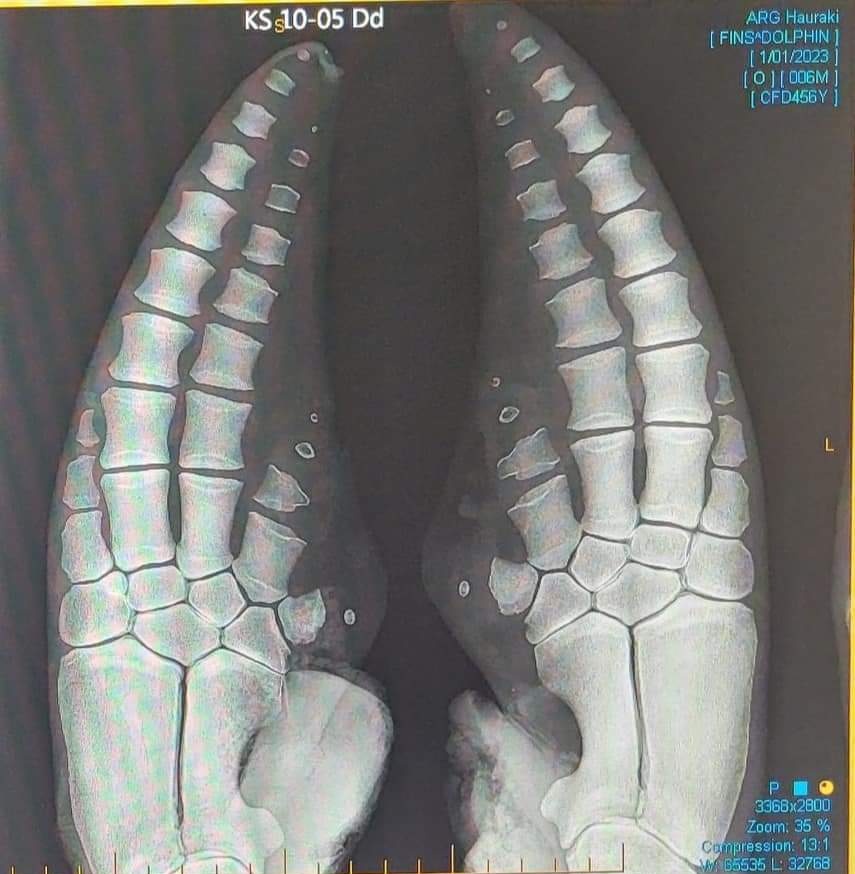

CERG PhD student Eva-Maria Hanninger is exploring the gems of our 25y pectoral forelimb collection to examine growth, aging and congenital anomalies in Delphinus #CetaceanEcologyResearchGroup Natural Sciences at Massey, #stranding #veterinaryanatomy